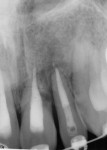

The patient presented 1 year later (2 years, 15 weeks post-trauma) (Figure 18 through Figure 20). Three months after his last follow-up appointment, orthodontic treatment had been started without any consultation. All teeth were non-tender to percussion and palpation. Percussion sounding was metallic on tooth No. 9, indicating ankylosis. Periodontal probing depths were within normal limits. Mobility was normal for all teeth except No. 9, which was immobile. Radiographic examination showed apical healing on teeth Nos. 8 and 10. Tooth No. 9 displayed a horizontal root fracture and moderate-to-severe external root resorption apically. The patient and his parent were advised of the findings.